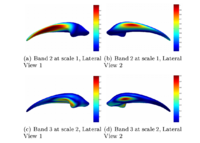

Re-Orientation Approach for Segmentation of DW-MRIThis work proposes a methodology to segment tubular fiber bundles from diffusion weighted magnetic resonance images (DW-MRI). Segmentation is simplified by locally reorienting diffusion information based on large-scale fiber bundle geometry. More... New: Near-Tubular Fiber Bundle Segmentation for Diffusion Weighted Imaging: Segmentation Through Frame Reorientation. Neuroimage, volume 45, 2009, pp. 123-132. |

Group Study on DW-MRI using the Tubular Surface ModelWe have proposed a new framework for performing group studies on DW-MRI data sets using the Tubular Surface Model of Mohan et al. We successfully apply this framework to discriminating schizophrenic cases from normal controls, as well as towards visualizing the regions of the Cingulum Bundle that are affected by Schizophrenia. More...